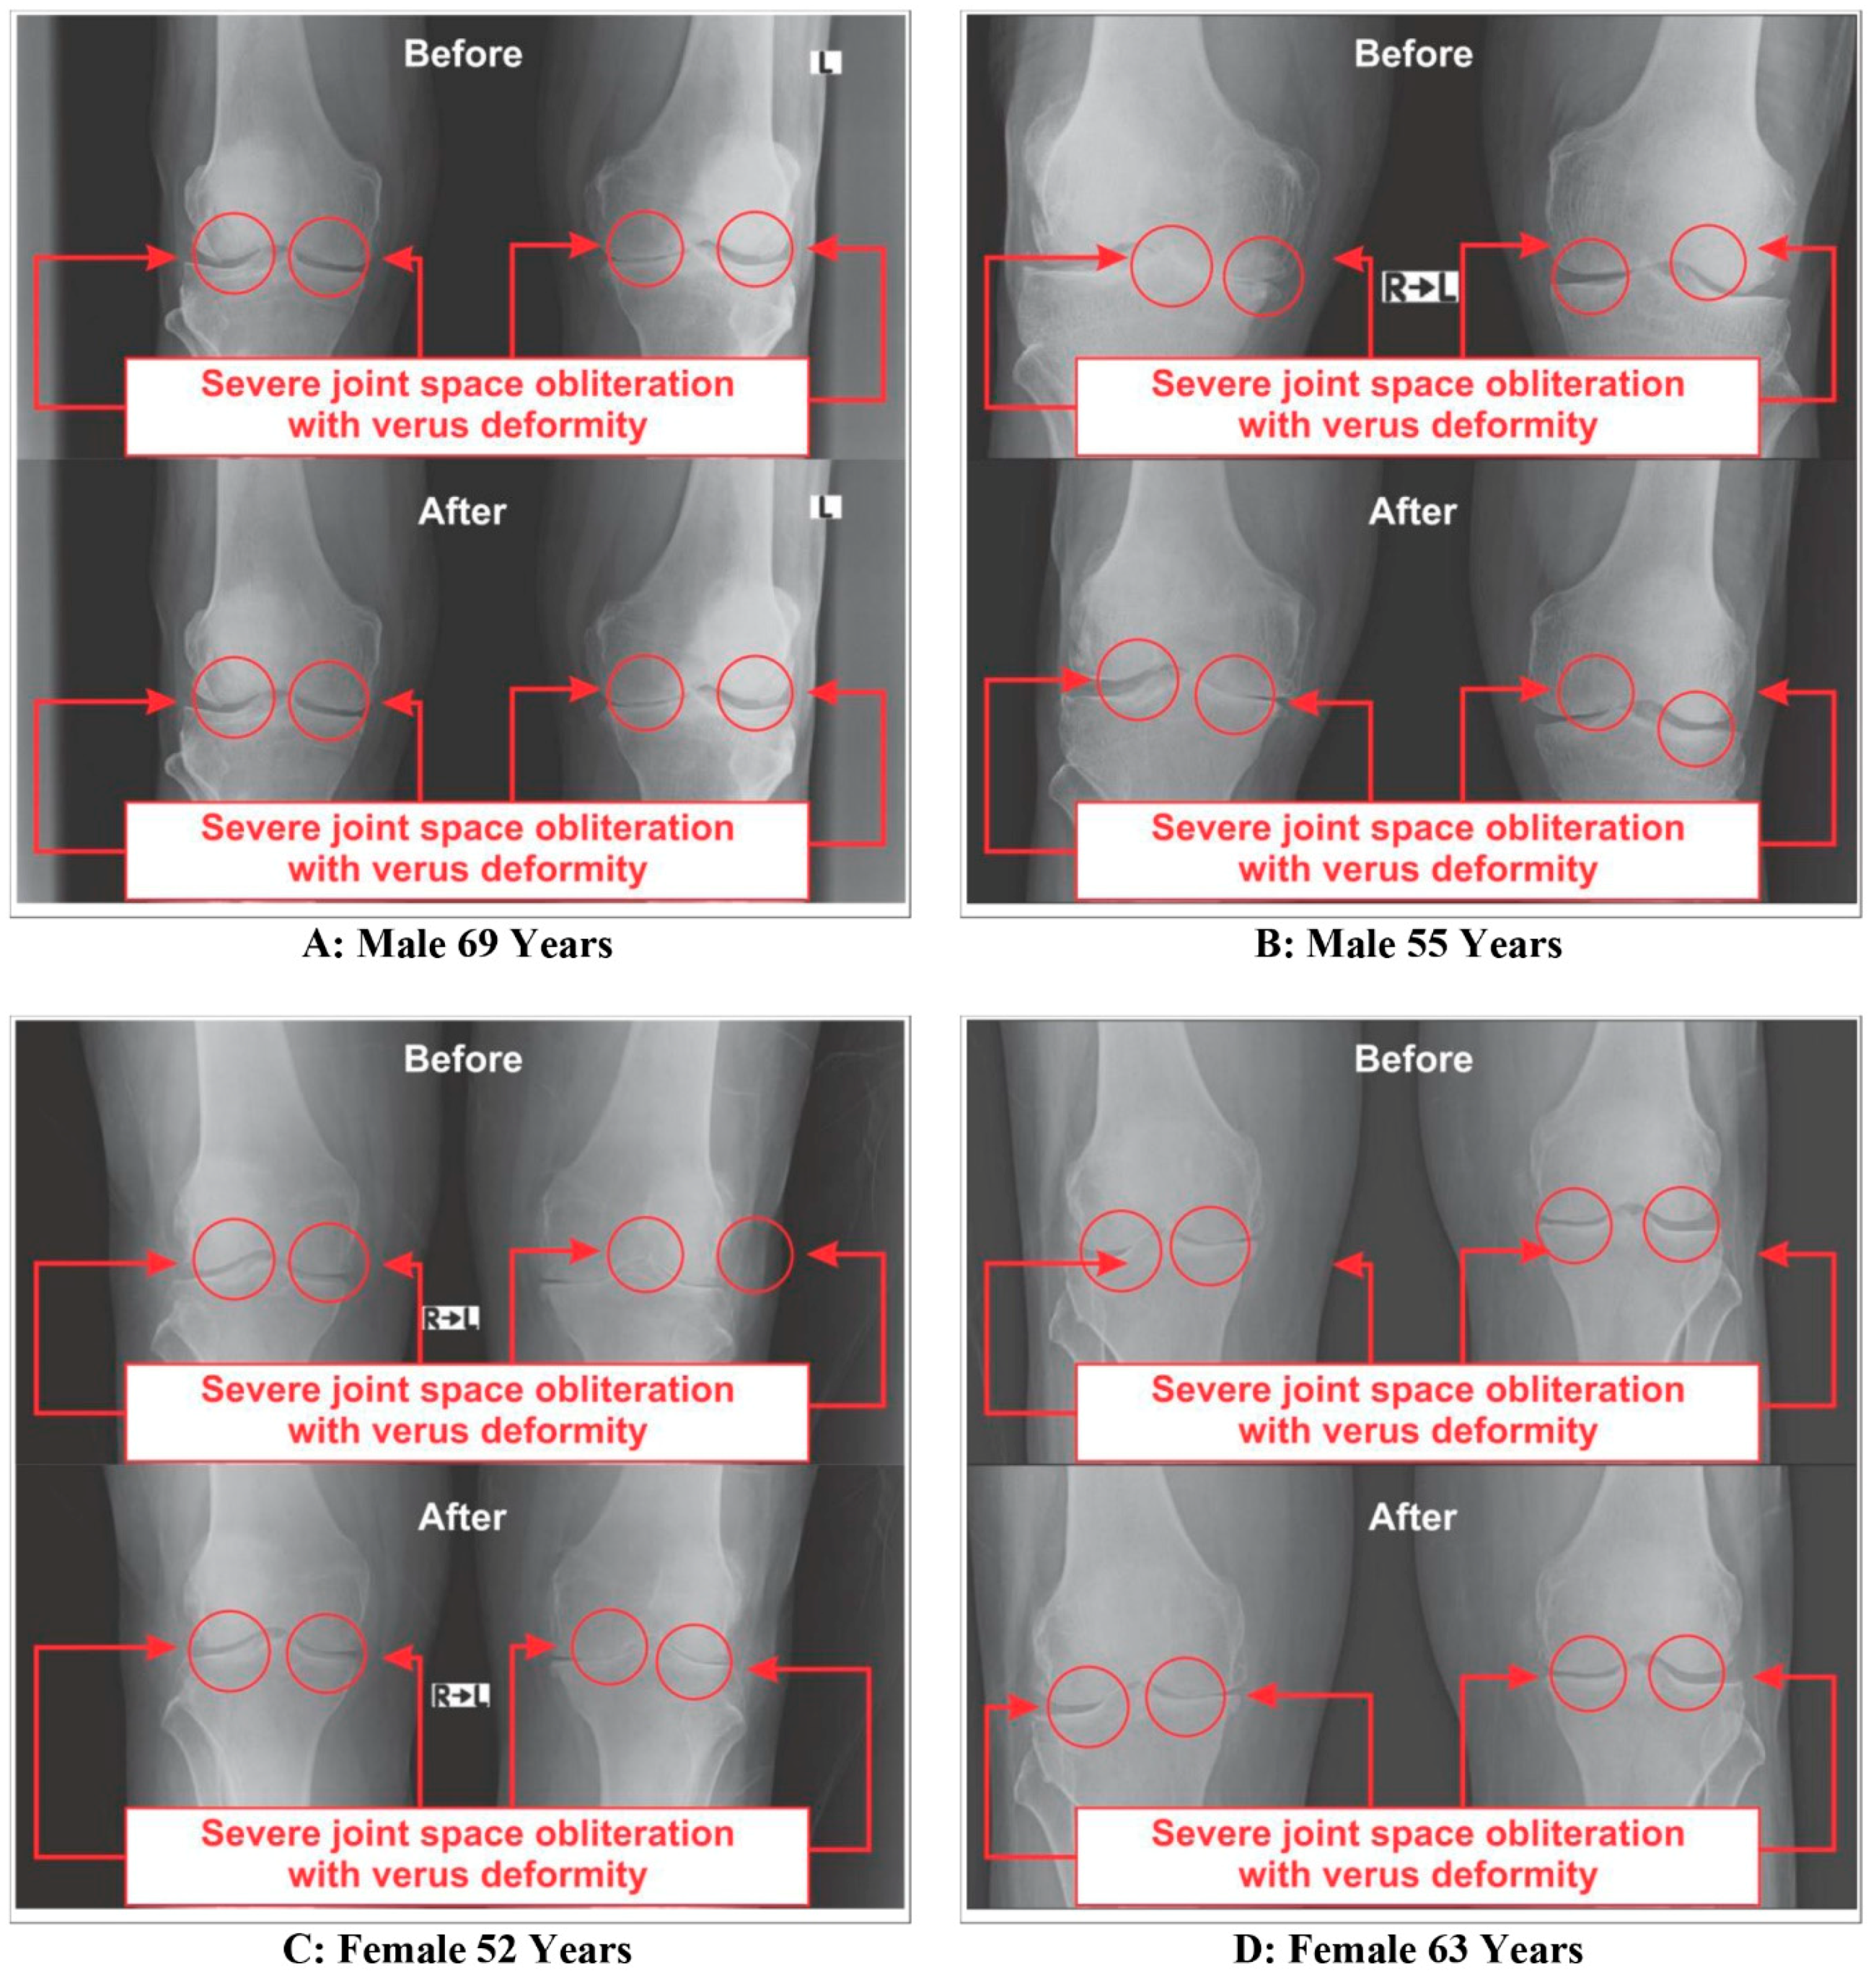

3.4. Improvements on Bone Health as per Radiological Images asAassessed by Kellgren-Lawrance Grading Scale

| Knee Joints | Gradation | Control Group (n = 45) | Experimental Group (n = 63) | ||||||

|---|---|---|---|---|---|---|---|---|---|

| Baseline | After Eight-Week | Baseline | After Eight-Week | ||||||

| Number | % | Number | % | Number | % | Number | % | ||

| KOA (Rt. knee) | Grade-0 | None | None | None | None | None | None | None | None |

| Grade-1 | None | None | None | None | None | None | 4 | 6.35 | |

| Grade-2 | None | None | None | None | None | None | 8 | 12.70 | |

| Grade-3 | 23 | 51.11 | 21 | 46.67 | 28 | 44.44 | 30 | 47.62 | |

| Grade-4 | 22 | 48.89 | 24 | 53.33 | 35 | 55.56 | 21 | 33.33 | |

| KOA (Lt. knee) | Grade-0 | None | None | None | None | None | None | None | None |

| Grade-1 | None | None | None | None | None | None | 3 | 4.76 | |

| Grade-2 | None | None | None | None | None | None | 7 | 11.11 | |

| Grade-3 | 19 | 42.22 | 17 | 37.78 | 27 | 42.86 | 31 | 49.21 | |

| Grade-4 | 26 | 57.78 | 28 | 62.22 | 36 | 57.14 | 22 | 34.92 | |